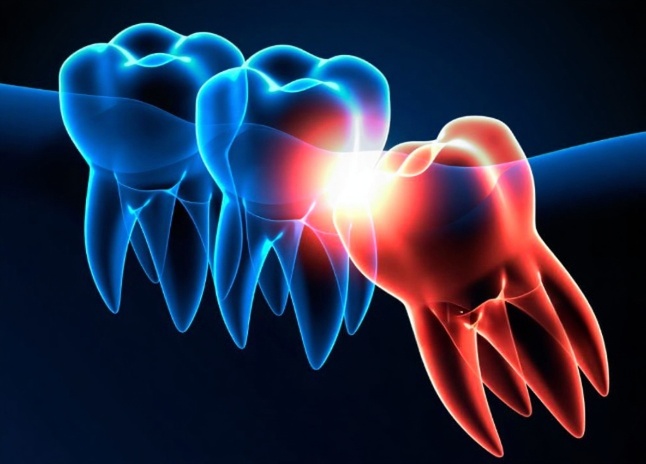

Oral Surgery

We provide minor oral surgeries — such as extractions or soft tissue procedures — with advanced techniques and gentle care, prioritizing safety, precision, and patient comfort.